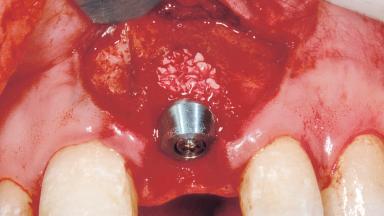

Bone Augmentation Horizontal|Simultaneous

Augmentation Materials Xenogenous|Membrane

Placement Protocol Immediate implant placement

Bone Volume Damage to one or more socket walls